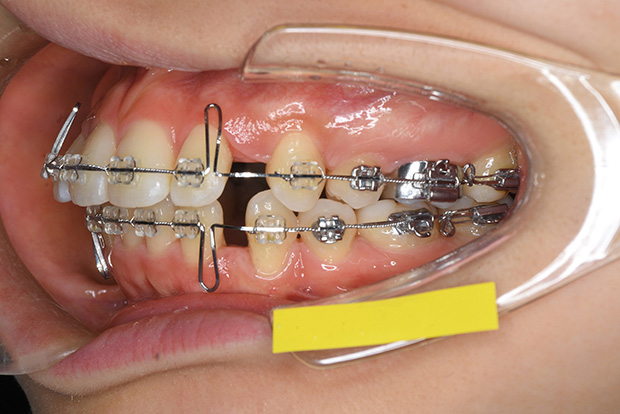

【ハーフリンガル】叢生 抜歯 上顎舌側マルチブラケット装置

| 主訴 |

ガタガタ |

||

|---|---|---|---|

| 診断名 |

右側Angle II級叢生 |

||

| 年齢 | 19歳 | 性別 | 女性 |

| 治療に用 いた装置 |

ハーフリンガル装置 (セミカスタム) | 抜歯部位 | 上顎両側第一小臼歯 下顎両側第二小臼歯 |

| 治療期間 ・回数 |

2年・24回 | 治療費 概算 |

約85万円 (調整料を含む) |

| 治療内容 詳細 |

歯科衛生科に入学し、自分の歯ならびが気になり始めたとのこと。上の歯列のみ舌側矯正(裏側矯正)、下は表側の、ハーフリンガルで治療を行いました。 |

||

| リスク・ 副作用 |

装置による違和感。疼痛、歯根吸収など |

||